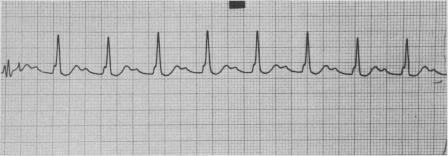

In a 53-year-old man with ventricular pre-excitation (normal PR interval, QRS interval of 0.12 seconds and delta-waves) acute inferior wall myocardial infarction was complicated by, successively, first-degree atrioventricular block, second-degree atrioventricular block (Wenckebach type) and complete heart block. The QRS pattern of pre-excitation was preserved throughout these events. The classification of ventricular pre-excitation is reviewed and the correlation between the various electrocardiographic patterns (the Wolff-Parkinson-White syndrome and its variants and the Lown-Ganong-Levine syndrome) and the anomalous conduction pathways of Kent, James and Mahaim are discussed. In this case the best possible explanation for preservation of pre-excitation during complete heart block was the existence of accessory fibres of Mahaim.

在一名53岁有室性预激(PR间期正常,QRS间期0.12秒且有δ波)的男性患者中,急性下壁心肌梗死相继并发一度房室传导阻滞、二度房室传导阻滞(文氏型)和完全性心脏传导阻滞。在这些过程中,预激的QRS图形一直存在。回顾了室性预激的分类,并讨论了各种心电图图形( Wolff-Parkinson-White综合征及其变异型和Lown-Ganong-Levine综合征)与Kent、James和Mahaim异常传导通路之间的相关性。在该病例中,完全性心脏传导阻滞期间预激得以保留的最佳解释是存在Mahaim副纤维。